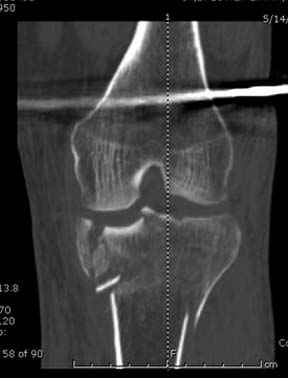

А нет ощущения, что плато "завалено" на варус?

293.jpg

21KB (22230 bytes)

Только вот линией вы вальгус показываете (норма)

Коллега, а нет ли снимков здоровой ноги, чтобы сравнить оси, если уж наши мнения разошлись?

Конечно, при таком повреждении всегда сложно выставить ось голени, знаю по собственному опыту, но все же?

Для адекватной оценки необходимо предоставить хотя бы по две проекции до и после синтеза. Снимки после синтеза - с захватом всей длины сегмента т.к. использовался гвоздь. По предоставленной одной некачественной проекции сказать можно только сказать что и решение, и результат спорные.

Отдельные переломы тибиал плато и перелом проксимальной трети большеберцовой кости отличаются от переломов тибиал плато с вовлечением диафиза. Здесь перелом тибиал плато типа Schatzker VI, полученный в результате высокоэнергетической травмы. Перелом метафиза образовал отрыв суставной поверхности от диафиза с вовлечением медиального и латерального мыщелков. Двухмыщелковые переломы из-за укрочения опасны развитием компартаментального синдрома, повреждением латерального мениска и связок.

Если там действительная импрессия, пустое место без структуральных заполнителей, кость или синтетические материалы, не восстановится, а образуется коллапс, и ось конечности поведет после нагрузки. Кроме того там возможно "болт стяжка"?, в медиальной стороне выступает за кортекс, можно было укоротить! Потом создается впечатление, что не соответствуют мыщелки большеберцовой и бедренной костей? Покажите снимок.